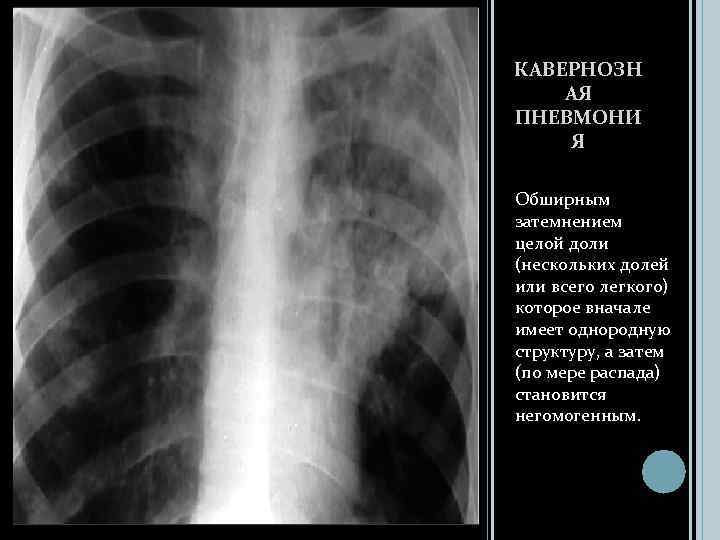

КАВЕРНОЗН АЯ ПНЕВМОНИ Я Обширным затемнением целой доли (нескольких долей или всего легкого) которое вначале имеет однородную структуру, а затем (по мере распада) становится негомогенным.